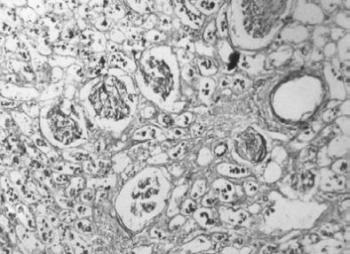

13. ábra. A veseartéria falában kitűnően feltüntethető az elasztikus membrán. 19 éves nő (meghalt 1801) veséje. Elastica-van-Gieson festés, 150× nagyítás